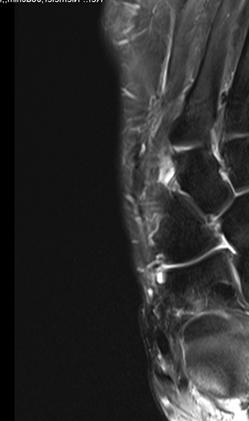

1.-Prä operatives MRT des linken Fußes vom Oktober 2016

Wegen einer konservativ nicht beherrschbaren Arthrose der linken Fußwurzel im Bereich der NC Gelenke 1 und 2 wurde die Indikation zur operativen Versteifung gestellt.